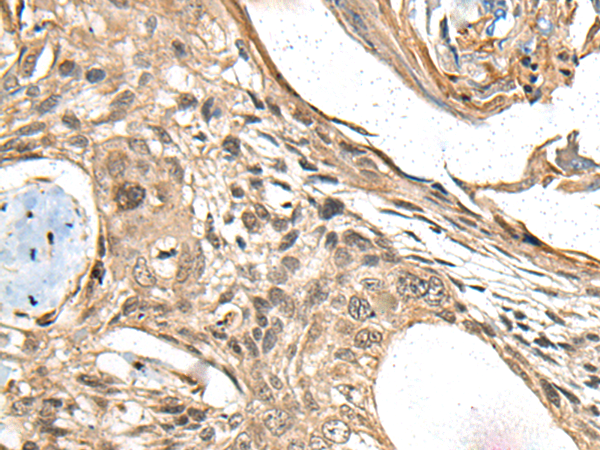

| IHC | 1/100-1/500 | Human,Mouse,Rat |